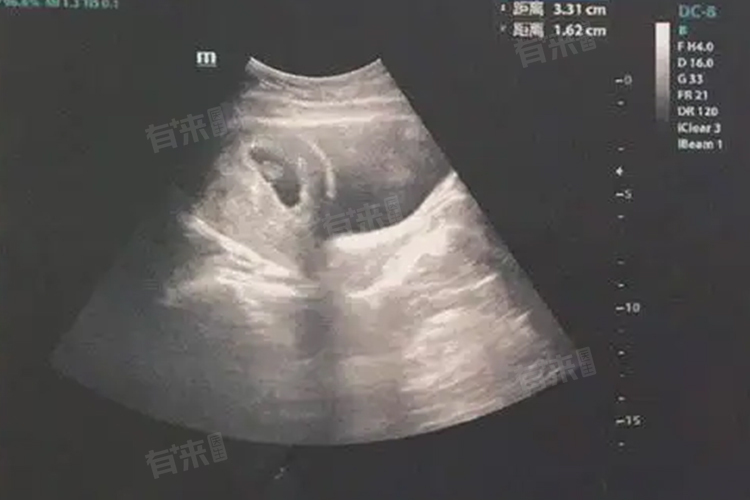

- 另外B超检查是观察胚芽发育情况的重要手段,但B超检查的时间点也会影响对胚芽出现时间的判断。一般妊娠6周左右进行B超检查,可以较为准确地观察到胚芽和胎心搏动。但需要注意,过早或过晚进行B超检查,都可能影响对胚芽发育情况的准确判断。